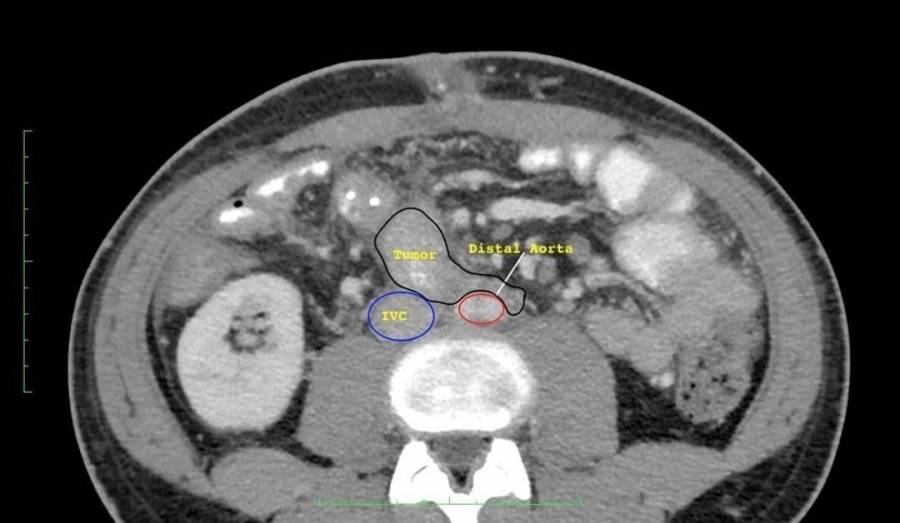

في عملية نوعية في الخدمات الطبيه الملكية، قام فريق طبي بمدينة الحسين الطبية مكون من أطباء الجراحة العامة والأورام وأطباء جراحة الأوعية الدموية والشرايين باستئصال كامل لورم ليفي نادر من الأمعاء في عملية جراحية اشتملت على استئصال واستبدال الشريان الأبهري البطني نتيجة امتداد الورم الى داخل جدار الشريان .

وفي التفاصيل ذكر العقيد الطبيب سهم القسوس مستشار الجراحة العامة وجراحة الكبد والأورام أن هذا الورم يصيب ما نسبته اقل من شخص من كل مليوني شخص، مبينا أن الورم كان مسببا لانسداد جزئي في الأمعاء، وأن عملية الاستئصال الكامل في هذه الحالة المتقدمة ليست ممكنه بدون استئصال الشريان الأبهري الرئيسي، بتشاركية مع أطباء جراحة الأوعية الدموية والشرايين.

وقال العقيد الطبيب جان الشيشاني مستشار جراحة الأوعية الدموية والشرايين أن امتداد هذا الورم الى داخل جدار الشريان وعدم استئصاله يؤدي في النهاية إلى نزيف شديد ووفاة المريض، مما شكل دافعآ رئيسياً اضافياً لاستئصال هذا الورم والشريان الرئيسي الأبهري، وان هذا الإمتداد نادرا جداً، وانه لا يوجد سوى عدد محدود من الحالات المشابهة المنشورة عالمياً .

وأشار المقدم الطبيب محمد الرشايدة مستشار جراحة الأوعية الدموية والشرايين أن الصور الطبقية وفحوصات الأنسجة التي تمت بعد إجراء العملية بينت الاستئصال الكامل للورم، و أن المريض ستتم متابعة حالته المرضية بشكل دوري بعد ان تماثل للشفاء و غادر المستشفى بصحة جيدة.